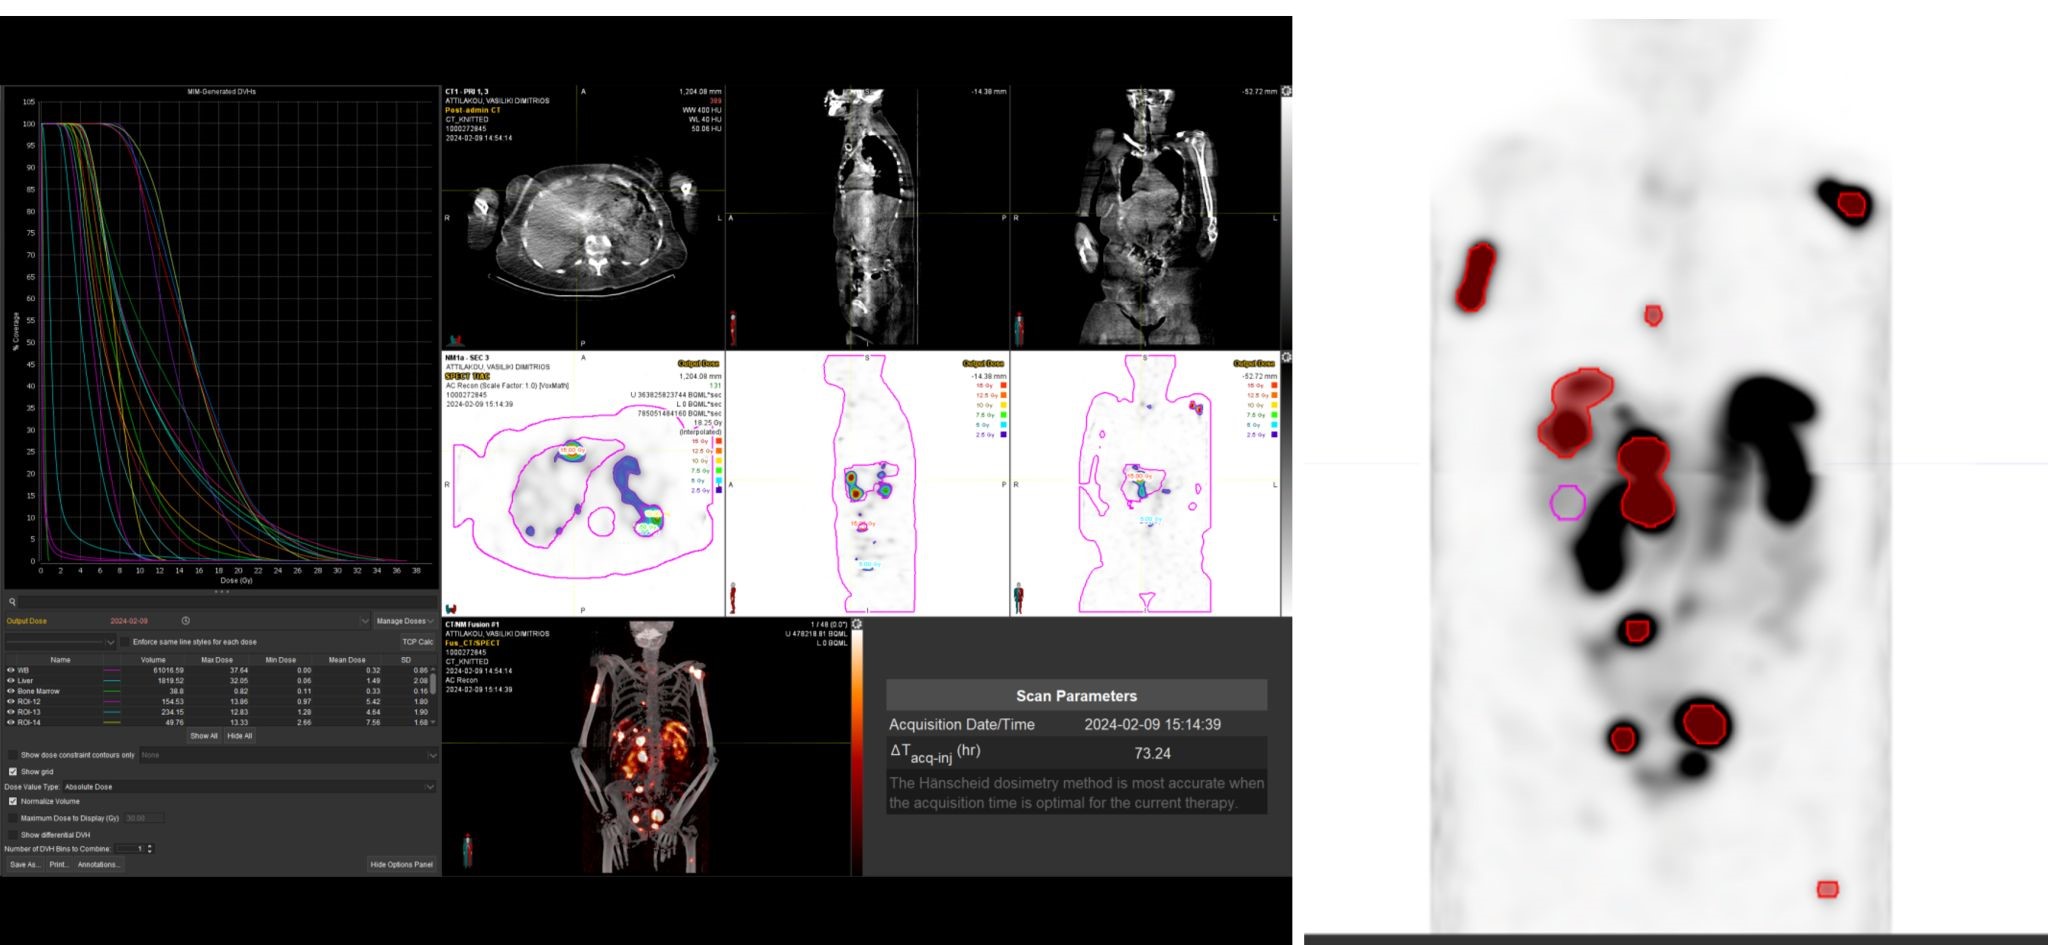

Η αξία της μεταθεραπευτικής δοσιμετρίας

Με τη SPECT‑CT ποσοτικοποίηση υπολογίζουμε απορροφούμενες δόσεις σε όγκους και όργανα‑στόχους (νεφροί, σιελογόνοι, ήπαρ, μυελός κ.ά.). Αυτό:

Σημείωση: Σύμφωνα με πρόσφατες κλινικές εργασίες/σειρές ασθενών – όπως οι LUMEN‑2 (για ΝΕΤ) και νεότερες μελέτες σε PSMA‑στόχο – η ποσοτική δοσιμετρία συσχετίζεται με την έκβαση και βελτιώνει τον θεραπευτικό σχεδιασμό.

Με βάση τα σύγχρονα Guidelines όλων των διεθνών ογκολογικών εταιρειών η μεταθεραπευτική απεικόνιση είναι προαπαιτούμενο για την έναρξη-συνέχιση της θεραπείας και το βέλτιστο αποτέλεσμα αυτής.